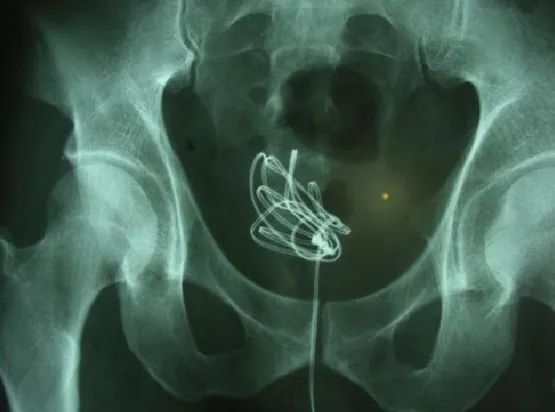

磁力珠丨参考文献10

膀胱镜下彩色的磁力珠丨参考文献10成人膀胱异物,多是为了获得性满足